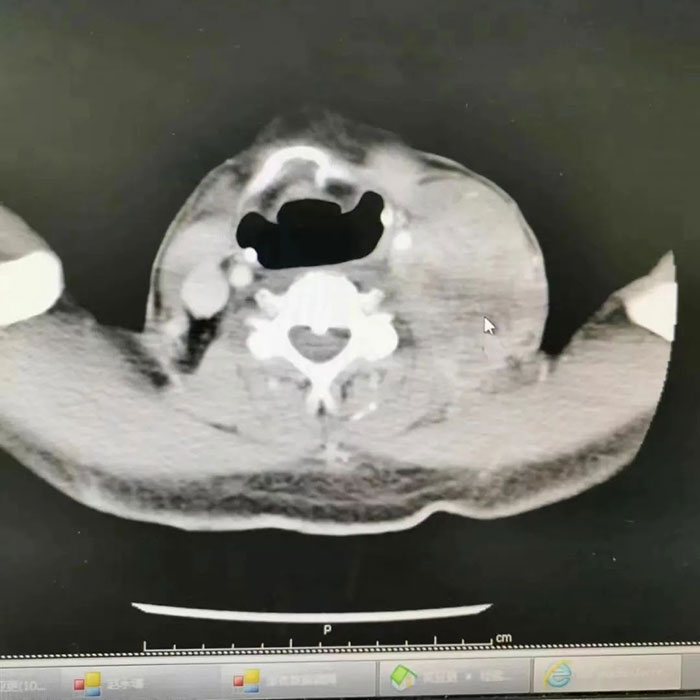

耳鼻喉科副主任李健接診后,發(fā)現(xiàn)患者腫瘤已長到了鵝蛋大小。經(jīng)了解,患者兩年前曾經(jīng)做過喉癌手術(shù),結(jié)合檢查結(jié)果得知目前手術(shù)區(qū)域沒有復發(fā),頸部的腫瘤應該是一個轉(zhuǎn)移癌,另外患者的對側(cè)甲狀腺有一個甲狀腺癌。

這個頸部復發(fā)癌非常棘手,它已經(jīng)侵犯了重要的血管神經(jīng)以及肌肉,最主要的是瘤子已經(jīng)將動脈包裹起來,動脈一旦破裂,輕則偏癱,重則植物人,甚至死亡,手術(shù)風險性極高;而如果采用傳統(tǒng)治療方式,定期來院放化療,雖然保險,但將面臨長期疼痛。

子女實在看不了父親遭受如此痛苦,在與專家反復研究父親的病情后,決定接受手術(shù)治療,為父親爭取更好的生命質(zhì)量。為了保證手術(shù)萬無一失,耳鼻喉專家團隊制定了嚴密的手術(shù)方案,一旦術(shù)中頸動脈破裂,會建立引流,即用一個管子將動脈下方的血引流至上方,夾閉切掉中間的一段,用周圍的靜脈代替,從而重建動脈。